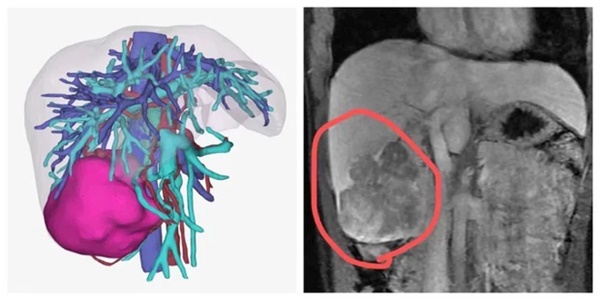

Tái tạo 3D và hình ảnh MRI của Tiểu Lý